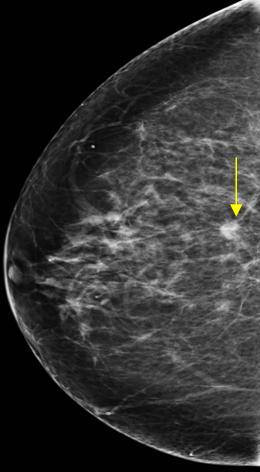

Ung thư vú

Ung thư vú - Ảnh 5

» Thông tin: Nữ giới – 62 tuổi.

» Lâm sàng: Kiểm tra sức khỏe.